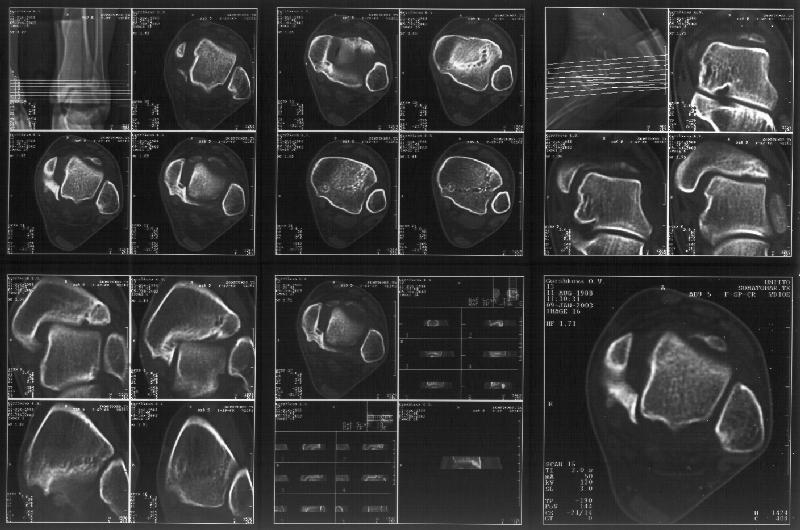

Отправитель: Alexander Chelnokov 19 Январь 2003, 22:34

Сегодня пациентке сделали сравнительную КТ. А ксиальные и Фронтальные срезы приложены. Ваше мнение?

Фронтальные

Аксиальные

На КТ я попытался изобразить скромными своими способностями (А)- место перелома, (С)- нормальный суставной зазор меж тараном и тремя его маллеолами. (В)- образовавшийся в результате перелома широкий раза в три зазор, позволяющий, по-моему, сублюксацию тарана при ходьбе. В свете данных КТ, критически важных, я бы предложил вертикальную остеотомию места перелома

задне-внутренним подходом и фиксацию мед. маллеола прижатым к тарану с помощью тонкого compression screw. После этого гипсовый сапожок и немедленное расхаживание ноги.